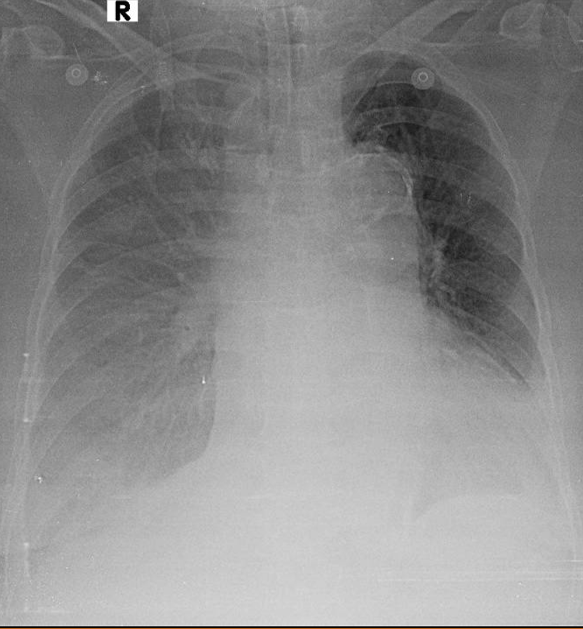

1-Tràn dịch màng phổi hai bên 2-Cung động mạch chủ dãn 3-Cung động mạch chủ đóng vôi 4-Bóng tim lớn 5-Có ống thông nội khí quản